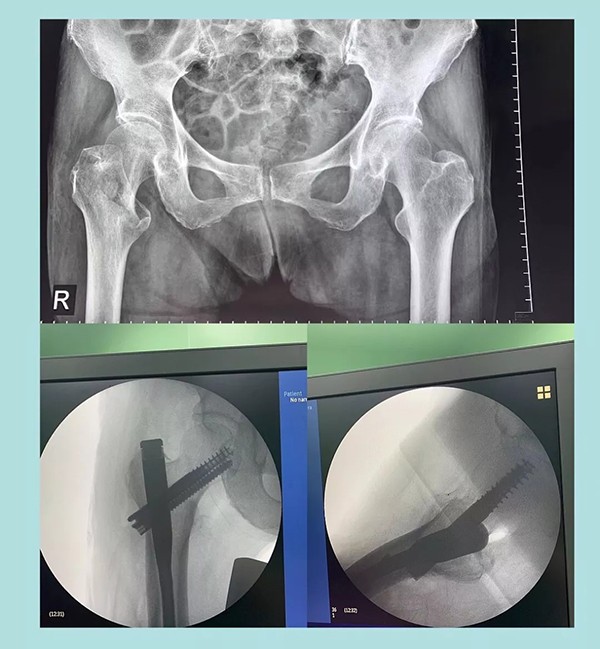

幾天前,蒲奶奶不小心摔了一跤倒地不起,到家附近醫(yī)院檢查后被診斷為右側(cè)股骨粗隆粉碎性骨折。醫(yī)生告知家屬,這種骨折對于老人來說非常棘手,建議保守治療。為提高老人生活質(zhì)量,家人商量后決定放手一搏,在打聽到我院關(guān)節(jié)科對這種病例治療效果非常理想后,立即轉(zhuǎn)往我院。

經(jīng)過內(nèi)科疾病的治療調(diào)理,總體符合手術(shù)條件后,羅軍主任帶領(lǐng)手術(shù)團隊為老人實施了閉合復(fù)位Intertan髓內(nèi)釘微創(chuàng)手術(shù)。為避免全麻對肺功能的影響,術(shù)中沒有使用常規(guī)的全麻氣管插管,而是采取神經(jīng)阻滯麻醉。術(shù)前老人嚴(yán)重貧血,為盡可能減少術(shù)中出血,手術(shù)采用微創(chuàng),且在半個小時內(nèi)順利完成。術(shù)后老人沒有明顯疼痛,術(shù)后一周即下地行走。